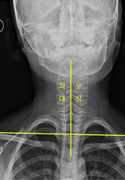

· 측만증치료

척추가 바르지 못한 아이들(소아)과 성장기 청소년에게 변형된 자세와 움직임 패턴을 인지하고,정상적인 자세의 회복을 도모하며 잘못된 자세에 의해 발생되는 손상을 방지합니다.

- 치 료 전

- 치 료 후